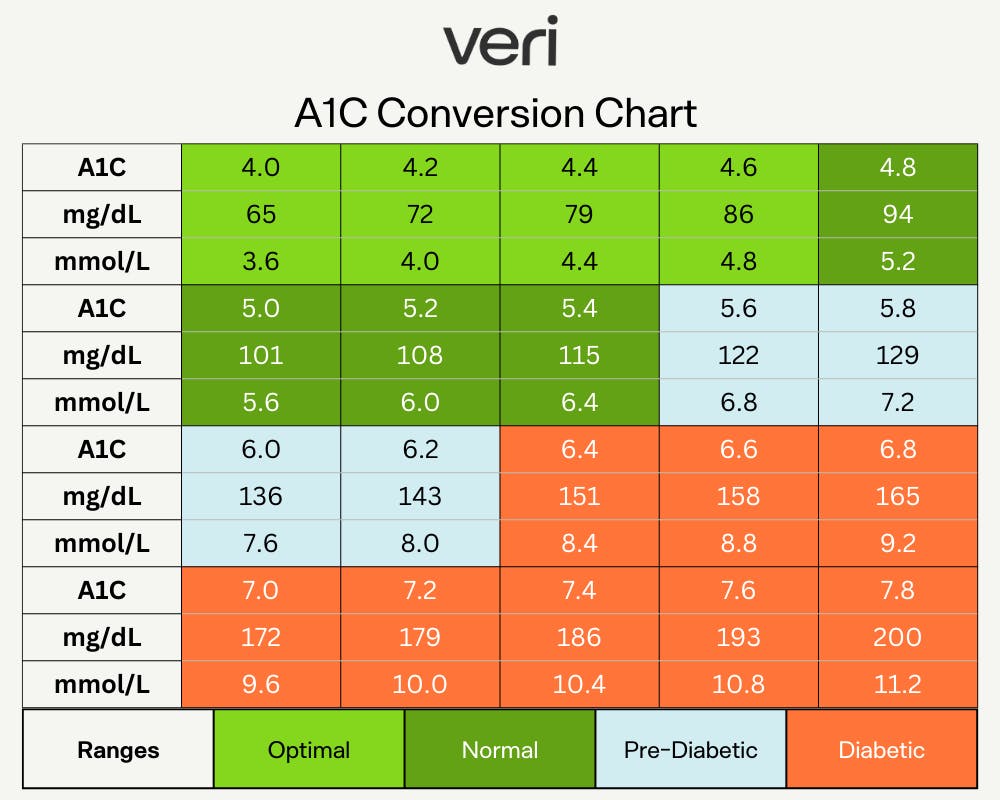

Blood Sugar Conversion Chart And Calculator Veri

https://images.prismic.io/veri-dev/fb6c92fd-83de-4cd6-a0b6-1526c71484f5_A1C+conversion+chart.png?auto=compress,format